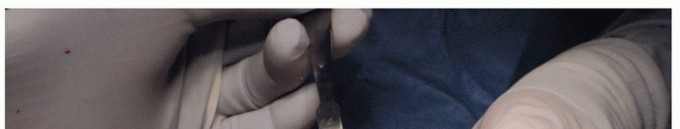

Tap the drill hole to the etched line (TECH FIG 2A-C).

Place the tapered screw of the HemiCAP DF implant, gaining purchase within the distal metatarsal bone. Bring the line indicator on the screwdriver just flush with the depth of the remaining articular surface level (TECH FIG 2D,E).

- TECH FIG 2 • A. A tap is used within the first metatarsal head, stopping at the etched line on the driver when flush with the plantar articular surface. B. A taper post screw is placed to the etched line when flush with the joint surface. C. Intraoperative use of tap to etched line using inferior aspect as reference point. D. Intraoperative screw placement. E. The screw is stopped when the etched line is flush with the remaining joint surface using the inferior aspect as the reference point. F. Screw can be advanced past etched line if bony decompression desired. Each one quarter-turn past the line equals 1 mm additional joint decompression. (continued)